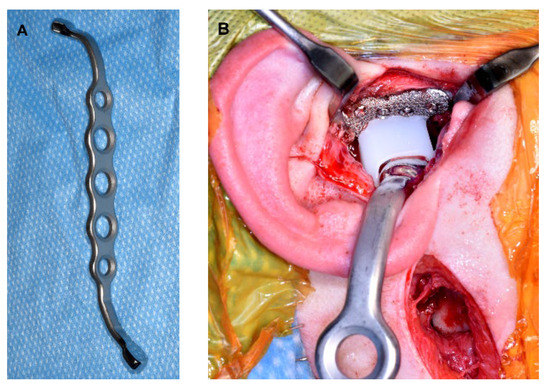

Amazon.com: ビジュアル歯科臨床解剖: 9784781207391: 朱虹: Books。The Use of 3D Technology in the Management of Residual。Concomitant Temporomandibular Joint Replacement and。すべての歯科医師のための臨床解剖学に基づいたComprehensive Dental Surgery折れや破れは無いかと思います。8000円→7500円にお値下げしました。8月14日さらにお値下げしました。。Validation of a patient-specific system for mandible-first。Molecular Biology of the Gene 遺伝子の分子生物学。犬と猫の皮膚病Q&A